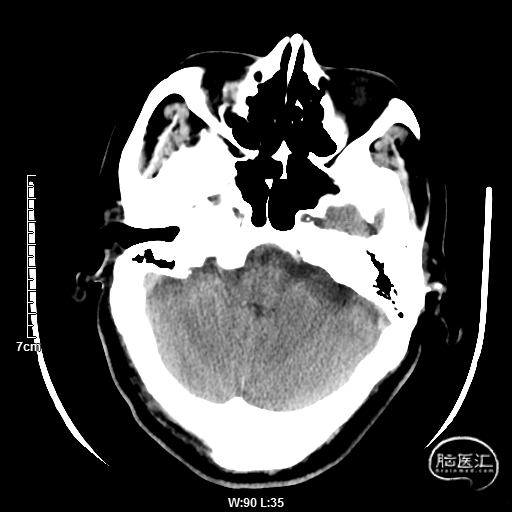

颅脑CT:未见明显缺血/出血病灶。

CTA提示:右侧椎动脉纤细,左侧椎动脉V1、V4段纤细。

MRI提示小脑缺血性改变。

术后CT:未见明显脑出血,双侧小脑低密度影。

术后CTA:Bridge药物支架形态良好,前向血流良好。

术后半年CTA:Bridge支架形态及贴壁良好,前向血流正常。